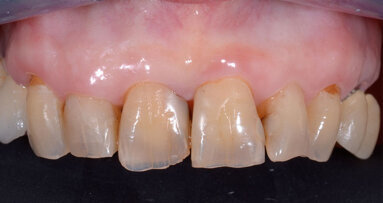

Una paziente di 69 anni si è presentata nel nostro studio. Tranne i denti 17 e 27, la mascella era edentula. I restanti denti non potevano essere conservati a causa della situazione parodontale. Una protesi provvisoria rimovibile è stata ancorata ai molari superiori. La paziente ha richiesto una protesi fissa per ripristinare definitivamente la funzione masticatoria e l’estetica. L’esame clinico e radiografico ha dimostrato che l’osso era sufficiente per posizionare gli impianti che avrebbero potuto sostenere una protesi fissa (Figg. 1 e 2), ed è stata progettata una protesi immediata con barra di ritenzione su sei impianti OsseoSpeed EV.

Dopo l’osteointegrazione degli impianti, i denti 17 e 27, che non potevano essere conservati, sono stati estratti. Dopo otto settimane di guarigione, la protesi provvisoria è stata rimossa e gli abutments Uni EV sono stati scoperti per prendere l’impronta finale (Fig. 10).